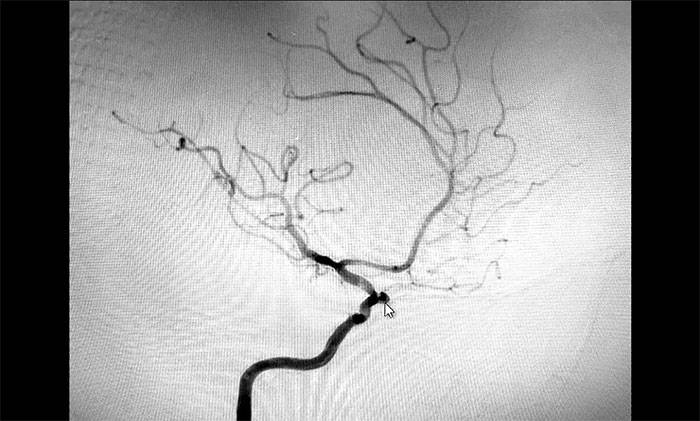

脑血管造影

但脑血管造影明确提示血栓影——很重要血管几近闭塞,患者症状随时